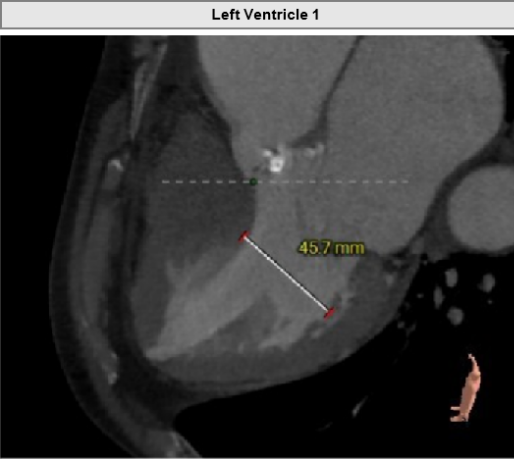

主动脉弓角度与宽度可,心脏水平夹角68°,横位心。

左室腔内径尚可,心室壁稍增厚。

升主动脉最大直径66.5mm。